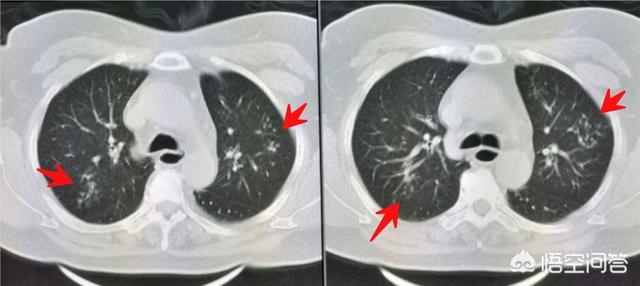

挂了呼吸科专家号,医生说做个肺部CT吧,这个年纪应当查一下:

胸部CT发现双肺多发小斑点状影,提示沿支气管扩散的肺内炎症。

同时我们注意到她的食管下段扩张(绿色圈):